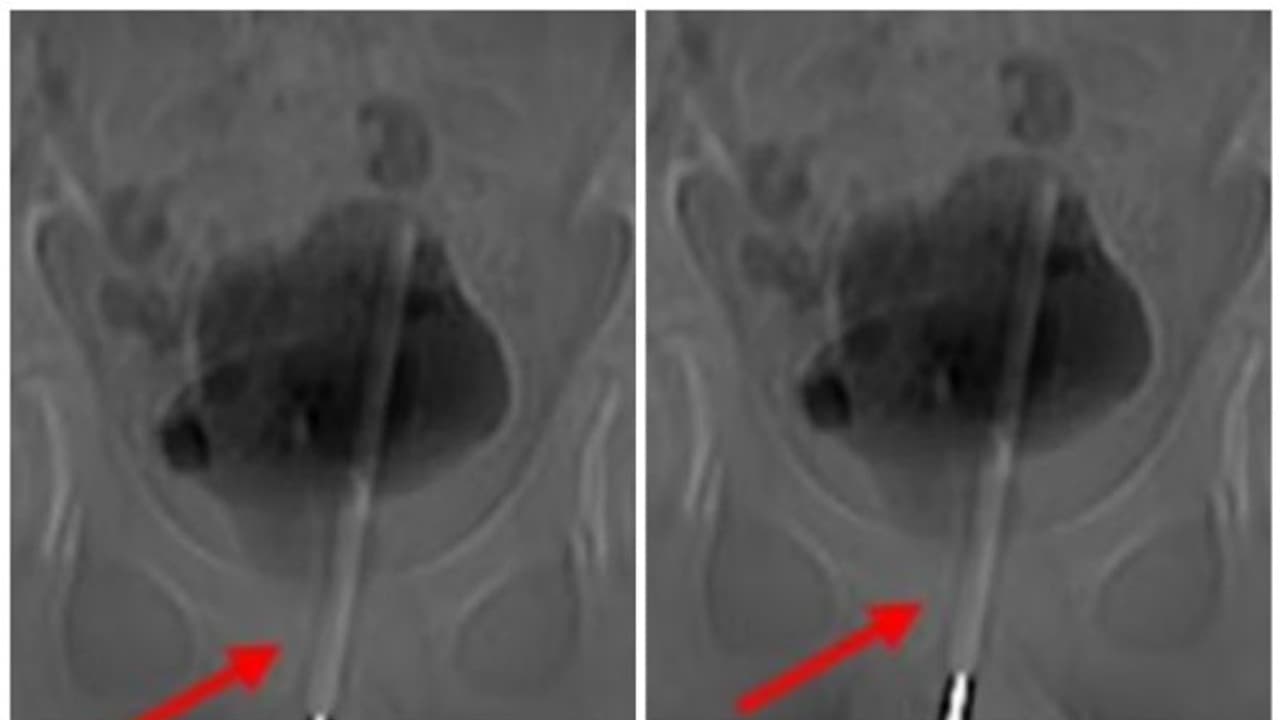

എക്സ്-റേയിൽ തെർമോമീറ്റർ മൂത്രനാളിയിൽ കയറിയതായും അത് കുട്ടിയുടെ മൂത്രസഞ്ചിയിൽ പ്രവേശിച്ചതായും കണ്ടെത്തി. താക്കോൽ-ദ്വാര ശസ്ത്രക്രിയയിലൂടെ കുട്ടിയുടെ മൂത്രസഞ്ചിയിൽ നിന്ന് തെർമോമീറ്റർ പുറത്തെടുക്കുകയായിരുന്നുവെന്ന് ശസ്ത്രക്രിയയ്ക്ക് നേതൃത്വം നൽകിയ ഡോക്ടർമാർ പറഞ്ഞു.

മൂത്രം സംഭരിക്കുന്ന മൂത്രാശയത്തിലേക്ക് അവർ ടിഷ്യൂവിൽ ഒരു ചെറിയ ശസ്ത്രക്രിയാ ദ്വാരം ഉണ്ടാക്കി തുടർന്ന് തെർമോമീറ്ററിനെ ശരിയായ കോണിലേക്കും സ്ഥാനത്തേക്കും കൈകാര്യം ചെയ്യാൻ ചെറിയ ഉപകരണങ്ങൾ തിരുകുകയും കീ-ഹോളിലൂടെ പുറത്തെടുക്കുകയും ചെയ്തു.